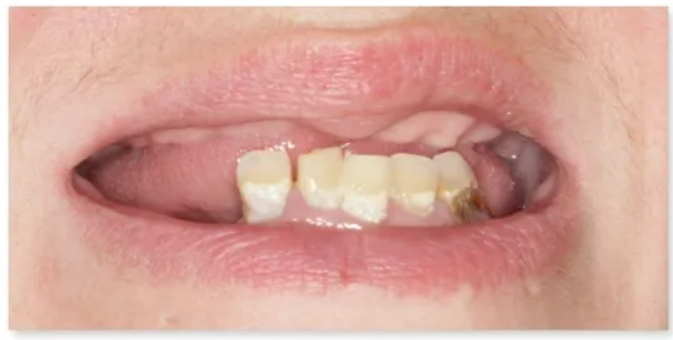

임플란트를 찾고 계신가요? 치아가 상실되면 가능한 빨리 임플란트 치료를 받으셔야 합니다.

치아를 상실된 채 그대로 두게 되면 치아 배열에 불균형과 턱뼈 손실, 잇몸질환 문제가 발생합니다.

특히, 치아가 빠진 자리에 턱뼈가 충분한 자극을 받지 못하면, 뼈가 약해지면서 얼굴 외형의 변화까지 생기게 됩니다.

이렇게 상실된 치아로 인해 외관상 좋지 않은 변형과 턱 관절 장애까지 유발하게 되면 더이상 되돌릴 수 없는 단계에 이르게 됩니다.